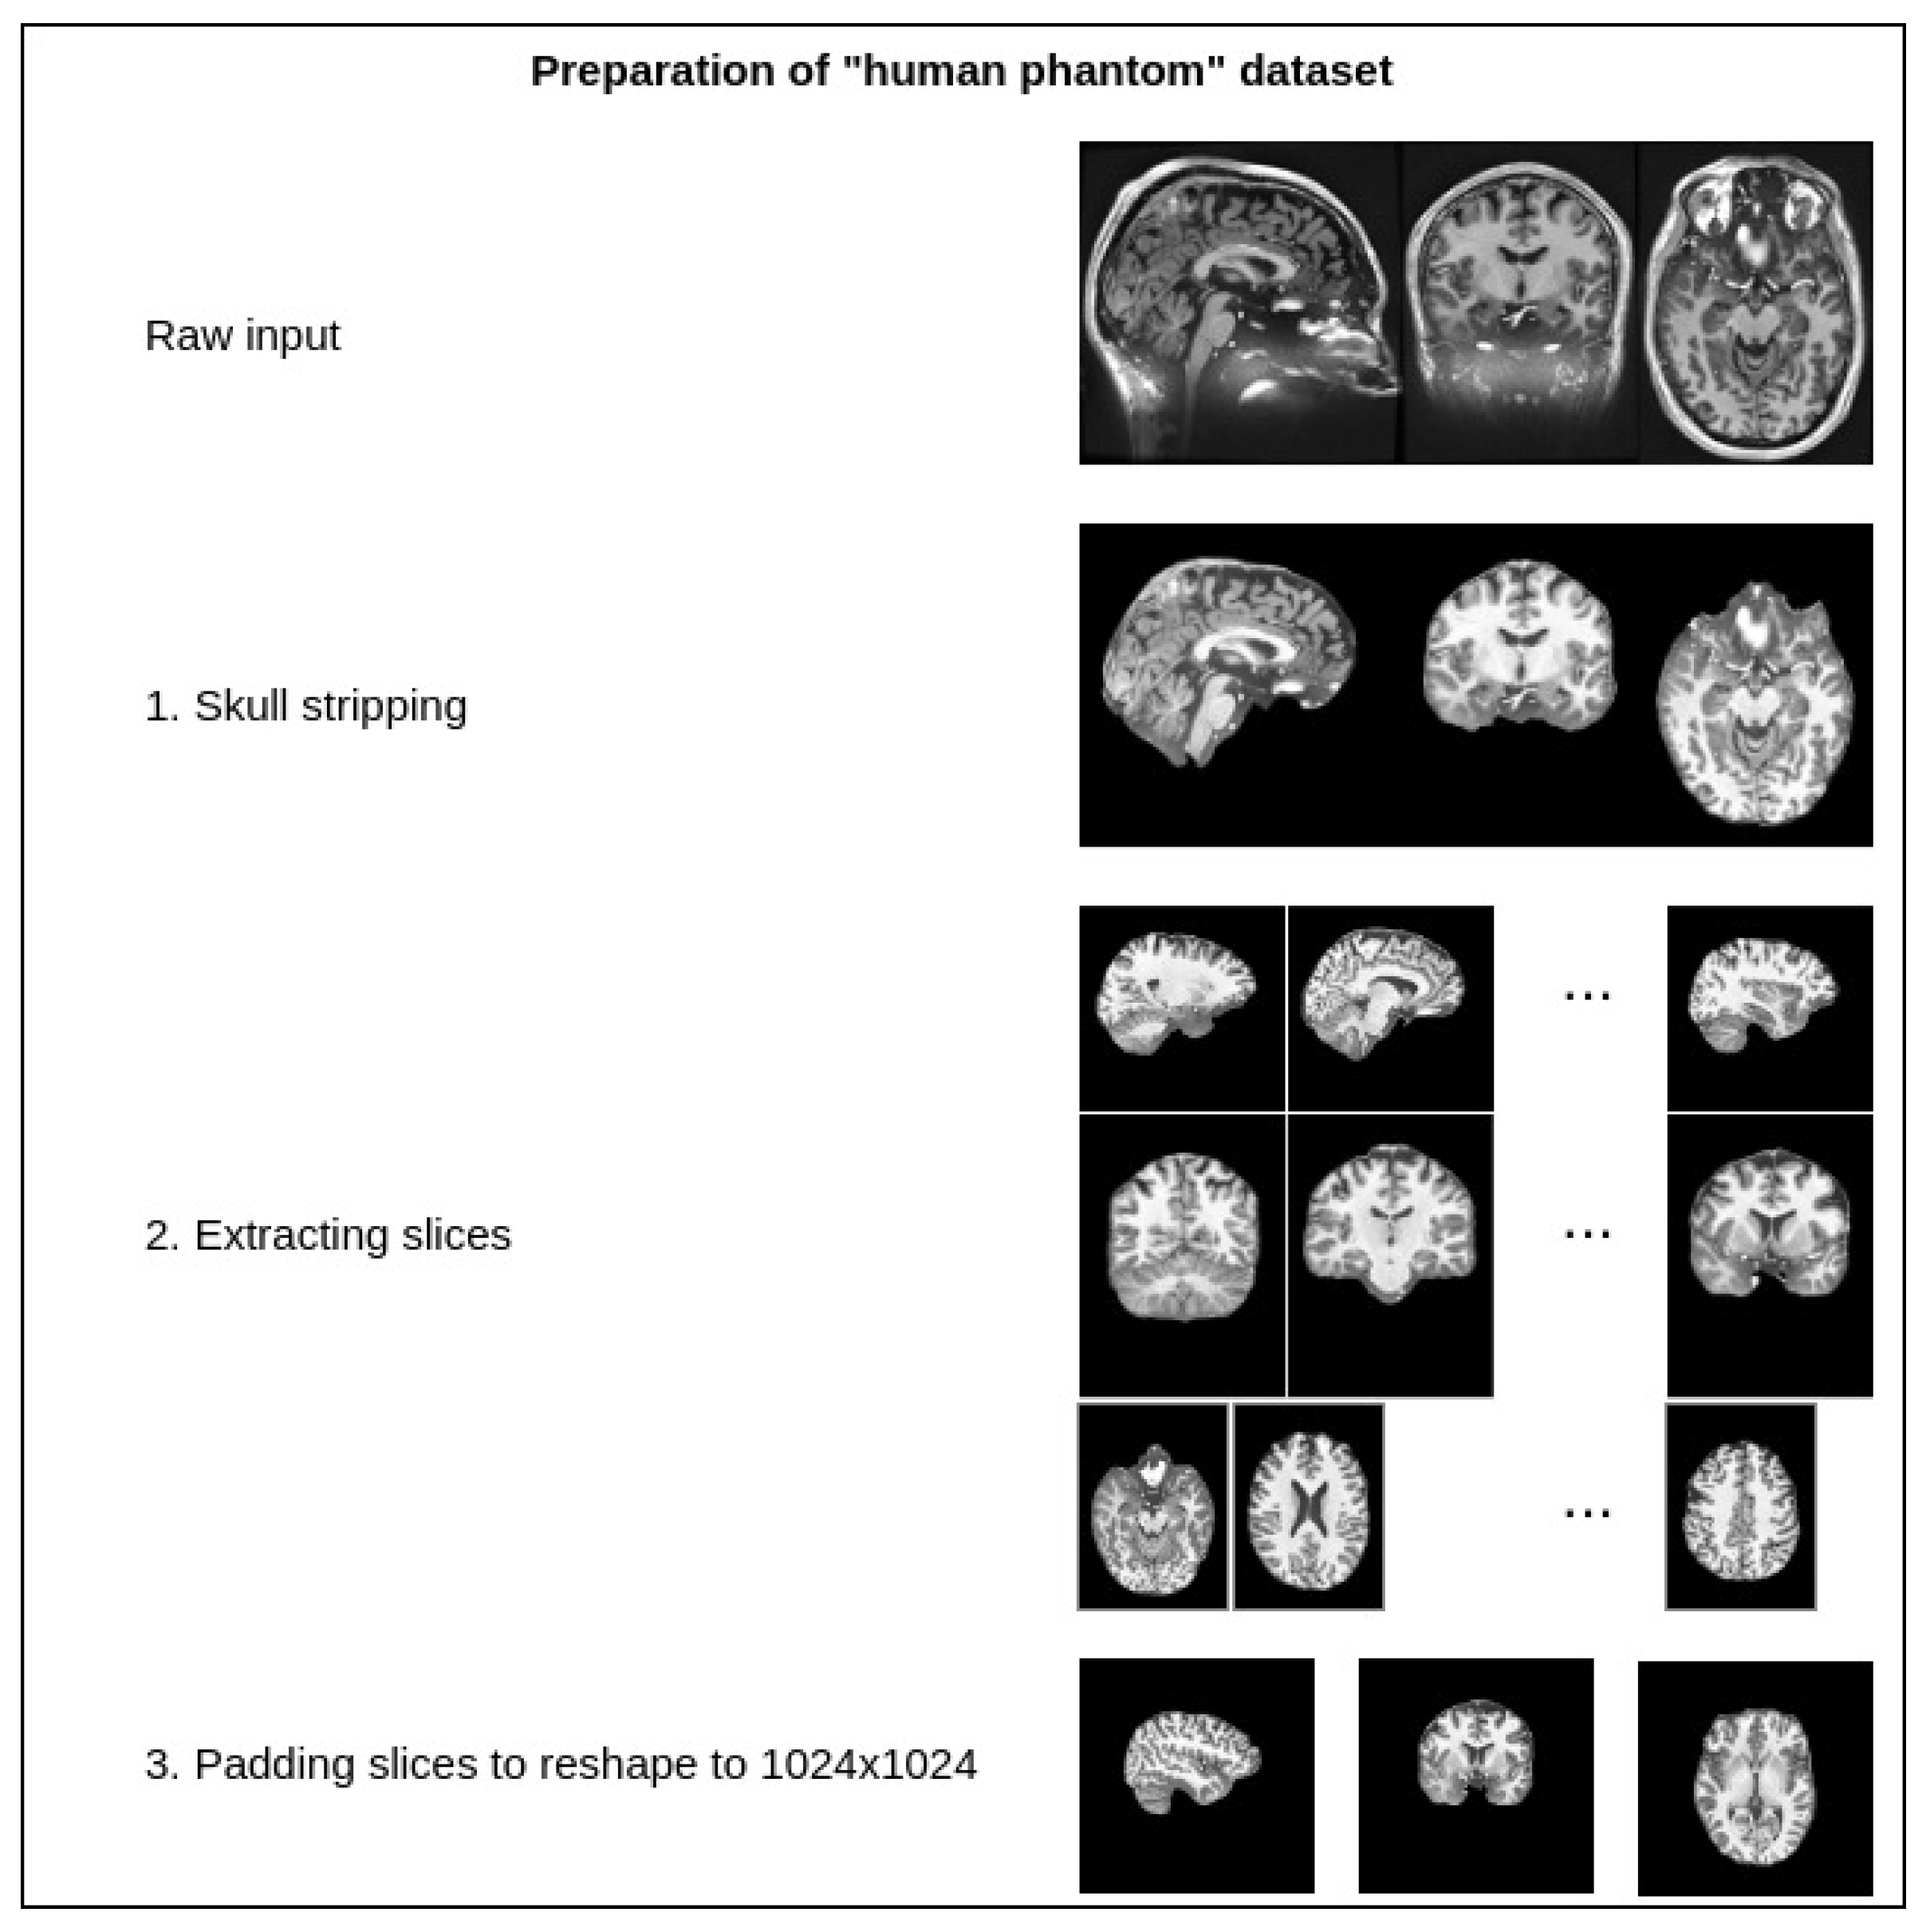

4.1. Experimentation Data

4.2. Implementation Details